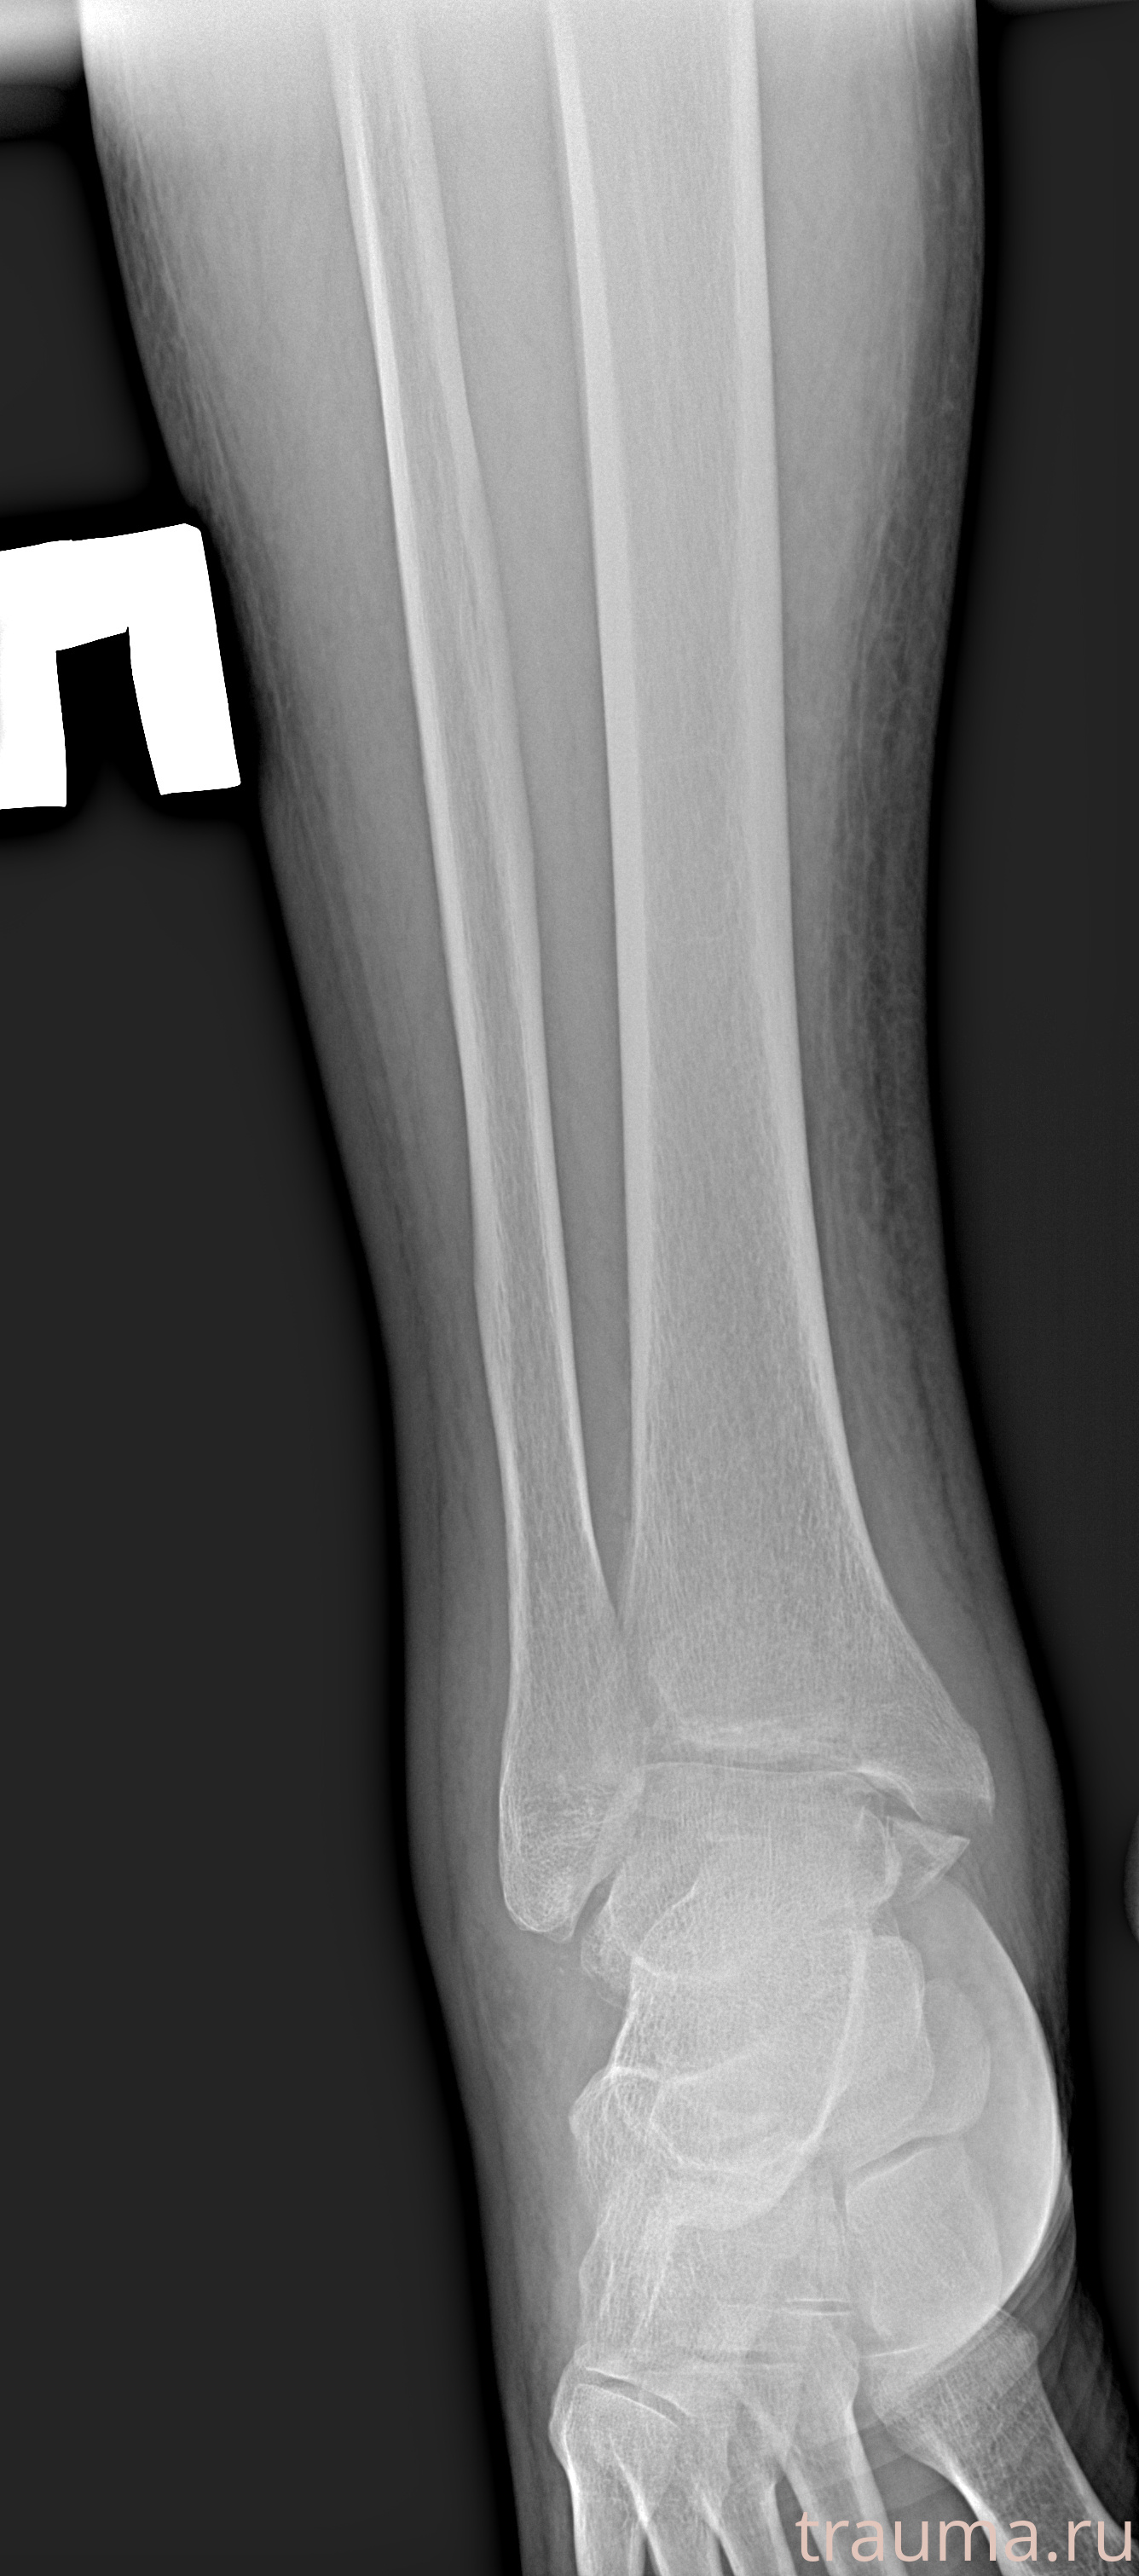

Рентгенограммы

Рентген на дому: по вашему адресу приезжает врач-рентгенолог, травматолог-ортопед с мобильным рентгеновским аппаратом, проводит диагностику травмы или заболевания, делает необходимые рентгенограммы, дает рекомендации по дальнейшему лечению. Получить качественные снимки в домашних условиях возможно благодаря уникальной методике, разработанной МосРентген Центром для института  Склифосовского